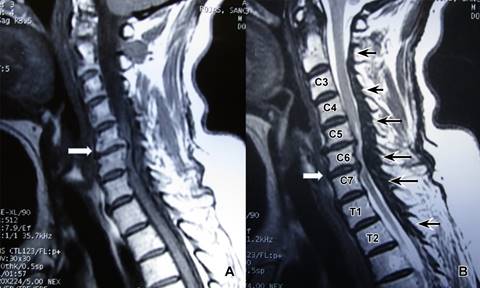

A la exploración inicial: paciente en silla de ruedas, con ausencia de equilibrio de tronco, frecuencia cardiaca de 80 l/min; frecuencia respiratoria de 16 r/min; tensión arterial de 110/60 mmHg, cráneo, cara y cuello al igual que pares craneales normales; tórax con ampliación y amplexación disminuidas, murmullo vesicular normal, ruidos cardiacos rítmicos sin fenómenos agregados; sensibilidad normal a nivel de C4 con hipoestesia profunda por abajo de horquilla esternal; abdomen, blando depresible, sin visceromegalias; reflejos cutáneo abdominales aumentados; miembros superiores con arcos de movimiento pasivos completos; examen clínico muscular para miembro superior derecho con calificación 0/5 de deltoides hacia abajo, miembro superior izquierdo deltoides en 4/5, bíceps braquial, coracobraquial y braquial anterior en 3/5, resto de musculatura en 0/5, por lo que se diagnostica lesión de neurona motora inferior en C5 derecha y C6 izquierda. Reflejos osteotendinosos tricipital, bicipital y estiloradial +++ bilateral; Hoffman bilateral presente; genitales normales, ausencia de reflejo anal; extremidades pélvicas: contractura en flexión de caderas, rodillas y tobillos por espasticidad, hipotrofia muscular generalizada de miembros pélvicos, examen clínico muscular en 0/5 bilateral; reflejos osteotendinosos rotulianos y aquileos +++, sensibilidad ausente. Babinski presente bilateral, conformando una lesión de neurona superior a nivel C6 derecha y C7 izquierda; siendo clasificada como grado V en la escala de Nurick. Se solicitó resonancia magnética mostrando: canal estrecho por presencia de ligamento amarillo hipertrófico de C2 a C7 (Figuras 1 a 3). Considerando tanto al área medular como a la del canal espinal como elipses, se utilizó fórmula para su cálculo (A = π × R1 × R2), así como al índice de Torg-Pavlov para valorar sus relaciones (Tabla 1). Con diagnóstico de mielopatía con nivel motor en C5, C6 y nivel sensitivo C5 derecha y C6 izquierda. Se interviene quirúrgicamente practicando laminectomía de las vértebras C3, C4, C5, C6 y C7 encontrando ligamento amarillo hipertrófico, el cual se reseca en su totalidad de C3 a C7, quedando el saco dural libre y latiendo, cerrando por planos. El estudio de patología reportó: cortes histológicos mostrando múltiples fragmentos de ligamento amarillo con mineralización y pérdida de la periodicidad de las fibras y cambios degenerativos moderados.

Figura 1: Imágenes de resonancia magnética de columna cervical, en corte sagital (A) ponderada en T1 y (B) en T2, mostrando en A canal estrecho asociado a degeneración discal y presencia de osteofitos posteriores de cuerpos vertebrales de C5-C6, en B se observa pequeña hernia discal C5-C6 y moderada en su tamaño a nivel de C6-C7. Existiendo hipertrofia del ligamento amarillo desde C2 a C7 con mayor volumen en C6, en femenino de 63 años.